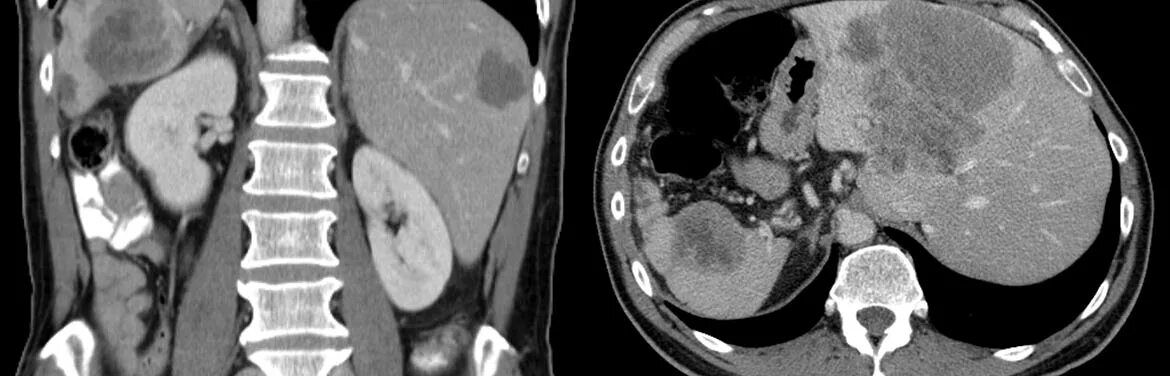

Метастазы при раке болят